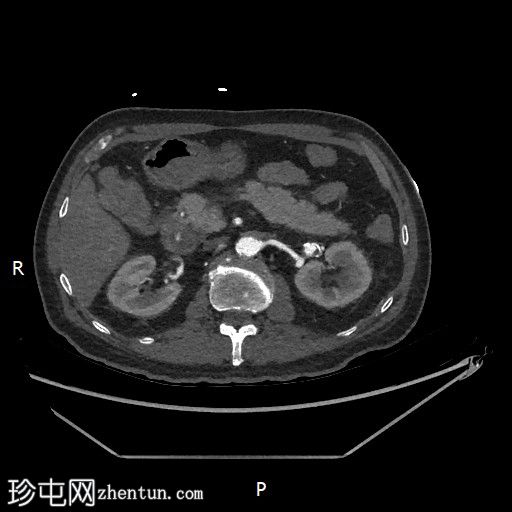

CT

轴位

平扫

轴位增强扫描

门静脉期